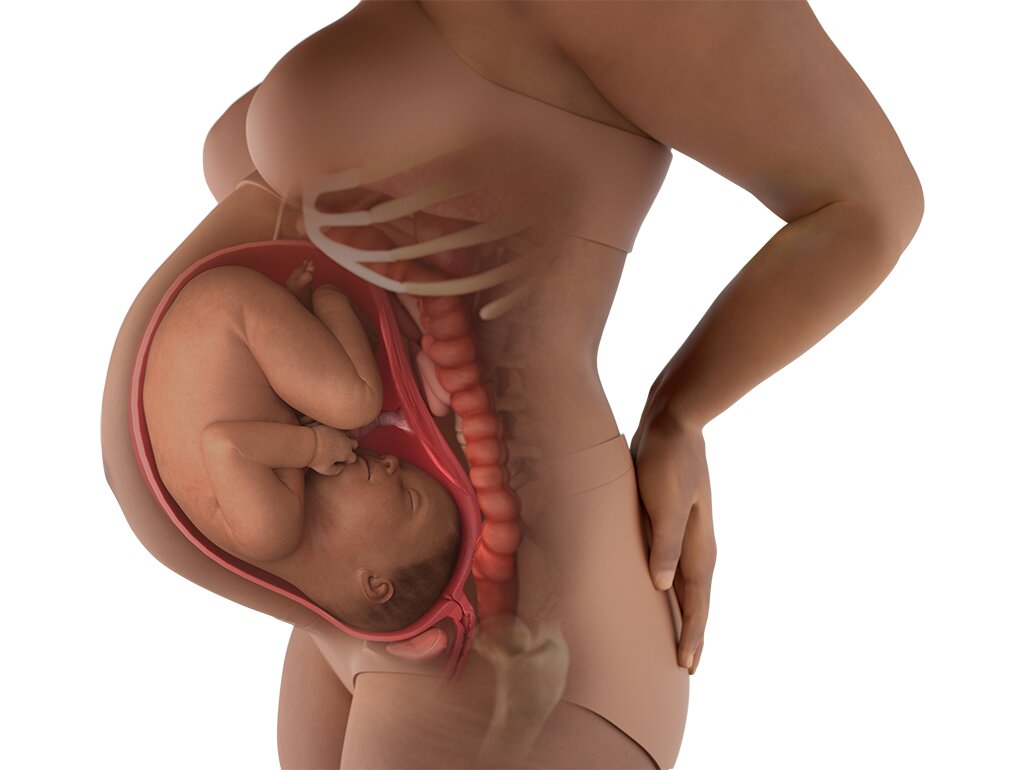

Perkembangan Janin 41 Minggu:

Minggu ke-41 disebut kehamilan lewat waktu. Sebagian ibu masih belum melahirkan pada usia ini, tetapi perlu pemantauan lebih ketat. Dokter biasanya akan memeriksa kondisi air ketuban, detak jantung janin, dan kesehatan ibu. Jika diperlukan, persalinan bisa dirangsang agar bayi lahir dengan aman. Pemeriksaan rutin sangat penting pada minggu ini.

Kondisi Perut Bumil Hamil 41 Minggu